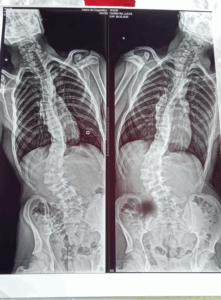

San Rafael: Una madre reclama por la demora en la operación de columna de su hijo y la falta de pago a prestadores de discapacidad

La historia de Sebastián Ferreyra es una de esas que ponen rostro y urgencia a

Leer más »